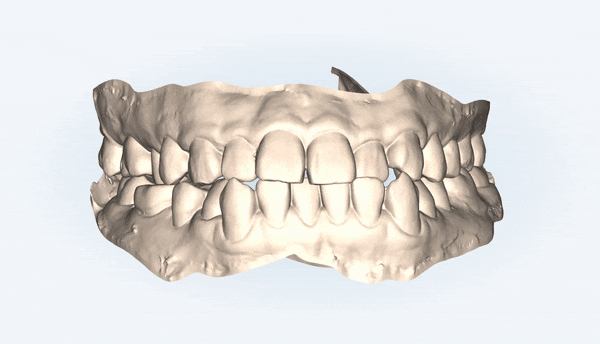

전체적으로 위,아랫니들이

제 위치를 찾으며 정리가 되었습니다!!

어금니들의 대이동이 끝이나고

클린체크의 예상대로 교정 마무리가 잘 되었어요!!

윗니와 아랫니 사이의 틈이 사라지고,

윗니를 덮고 있던 아랫니들이 제 위치를 찾으며 부정교합이 개선되었을 뿐만 아니라

정중앙선이 일치하도록 마무리 해드렸습니다 :)